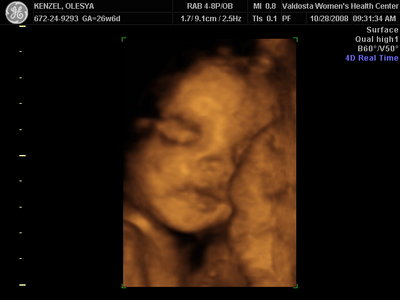

Ксюнь, а мы вообще не поняли. Она на всех фотках разная, да еще размытость такая. Пуповина то на носу болталась, то руками-ногами закрывалась. Главное что четкости нет совсем. Лоб у мужа тоже большой, а носы и губы зачастую на 3Д-4Д выходят разамазанно-пухло-приплюснутыми Поставлю для наглядности фотку моей средней-Джианки с 3Д УЗИ, там видно черты намного лучше и она на себя ту похожа сейчас, хотя родилась мне совсем на фото УЗИ не казалась похожей.

| Вложения: |

KENZEL,OLESYA_3.JPG [ 56.84 КБ | Просмотров: 1426 ]

Еще одна Джианнка:

KENZEL,OLESYA_5.JPG [ 60.02 КБ | Просмотров: 1511 ]

Катюш, какой прикольный бутузик ! Олесь, после фотки средней - точно прям похожи!